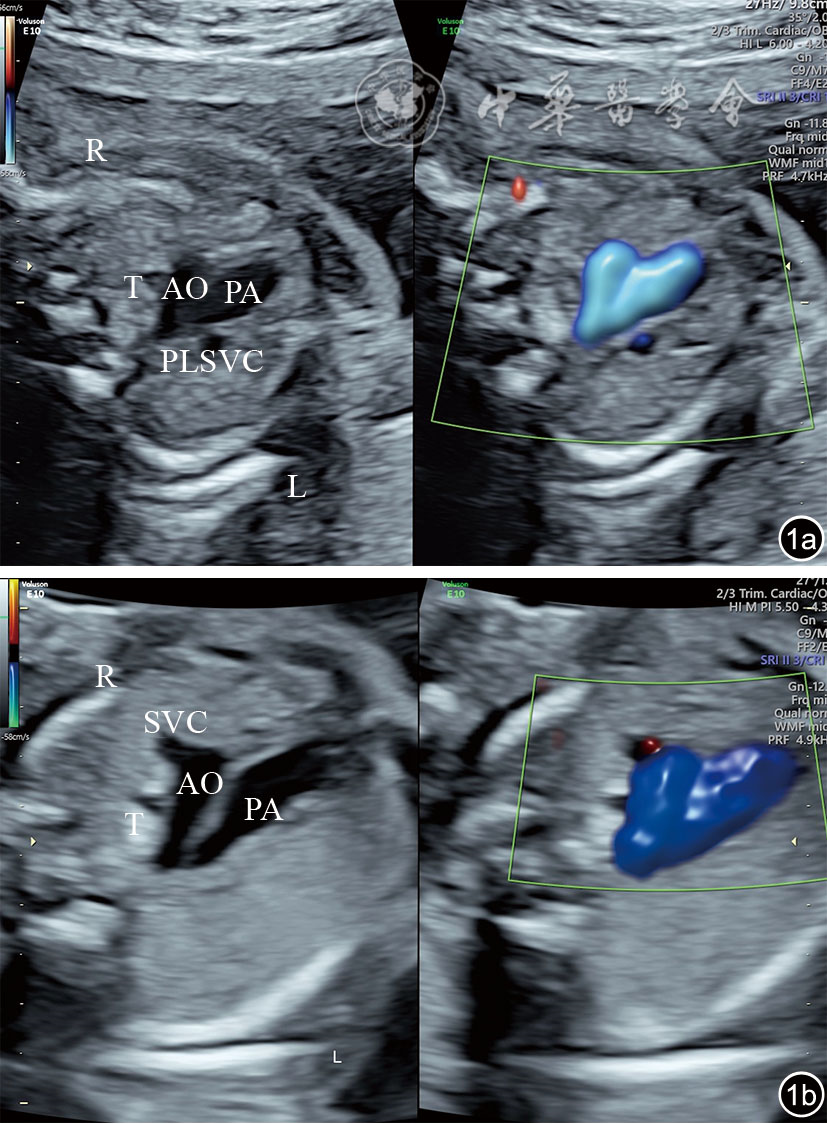

图1 永存左上腔静脉合并右上腔静脉缺如胎儿与正常胎儿三血管气管切面二维超声图像及彩色多普勒血流成像。图a为永存左上腔静脉合并右上腔静脉缺如胎儿图像,肺动脉左侧见一管状回声为永存左上腔静脉,主动脉右侧未见右上腔静脉;图b为正常胎儿图像,从左至右依次为肺动脉、主动脉、上腔静脉 注:AO为主动脉;PA为肺动脉;T为气管;PLSVC为永存左上腔静脉;SVC为上腔静脉;L为左侧